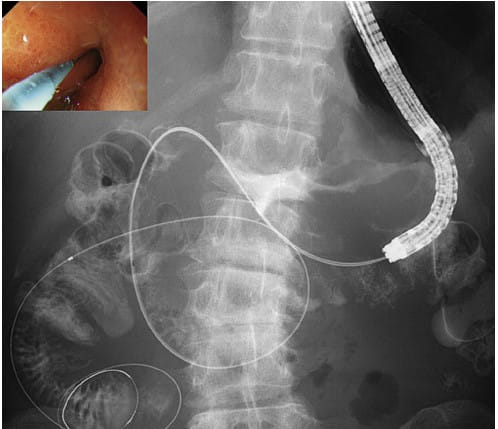

Endoscopic Ultrasonography (EUS)-guided anastomosis marks a significant milestone in the treatment of gastric outlet obstruction. This procedure enables the creation of a connection between the stomach and the jejunum, using a lumen-apposing metal stent (LAMS). The stent placement, which can be achieved directly or with balloon assistance under fluoroscopic and sonographic guidance, showcases the evolving precision in gastrointestinal interventions. Despite the limited experience, early data suggest promising outcomes, offering new hope to patients with this challenging condition.

The successful execution of EUS-guided procedures relies heavily on a suite of specialized equipment. This arsenal includes a fluoroscopy unit, a therapeutic echoendoscope, and essential accessories such as 19-G needles, ERCP cannulae, needle-knife catheters, guidewires, balloon dilators, LAMS, double-pigtail plastic stents, and biliary drainage catheters. The availability and proper use of these tools are paramount in performing these advanced interventions, ensuring optimal outcomes for patients.